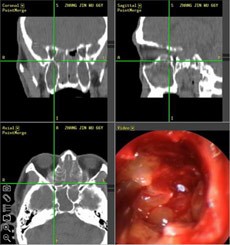

【典型案例】反复手术切息肉 复发导致嗅觉减退5年之久

张先生家住兰州,是典型的鼻窦炎患者,经常会出现鼻塞、流脓涕、头痛、等症状,去过多家医院,治疗结果并不理想,复发不说,到现在张先生的嗅觉已经严重减退,味道都快闻不出来了。

经推荐,跨省来到西安新城中大耳鼻喉医院耳鼻喉科治疗,入院后,经医生诊断并推荐使用“”,在鼻内窥镜的帮助下切除鼻息肉,术后经过10天后复诊并无复发现象。

(图为:鼻窦炎患者治疗现场) (图为:鼻窦炎治疗图谱)

[原理阐述]: “”技术以“CT片检查”和“STORZ鼻内窥镜”精准定位,借助“美国美敦力微创切割动力系统”和“美国杰西微创手术消融系统” 精确“扫净”四对鼻窦炎症,避免“漏诊盲区”、迁延其它鼻窦复发;同时功能性鼻腔术后修复和绿色技术,轻松清除额窦、上颌窦、筛窦和蝶窦等合并症,迅速恢复鼻部功能,治疗恢复期比同等手术缩短三倍,被称为“多窦一清”高端技术。